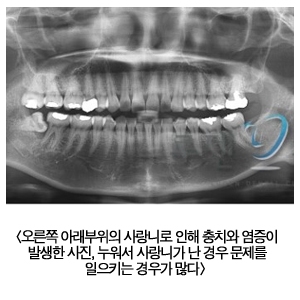

- 사랑니, 꼭 빼야 하나요